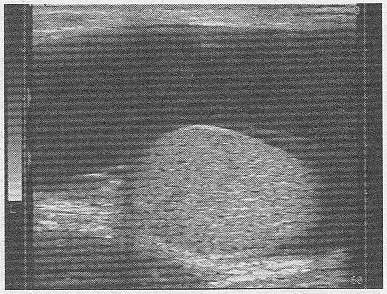

5.某患者陰囊超聲聲像圖如下,最可能的診斷為

正確答案:A 解題思路:陰囊內(nèi)見(jiàn)無(wú)回聲暗區(qū),睪丸附著于鞘膜囊的一側(cè),液體三面包繞睪丸周圍。